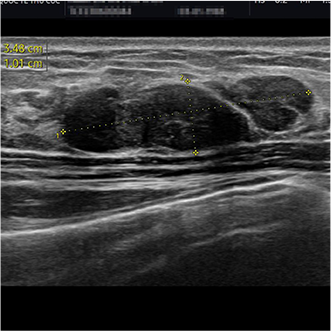

VABB (Vacuum-Assisted Breast Biopsy) là phương pháp điều trị u vú lành tính ứng dụng công nghệ cao. Bác sĩ sử dụng máy sinh thiết dao cắt quay dưới hướng dẫn của siêu âm để cắt và hút bỏ u ra ngoài qua lõi kim được chọc qua da thông qua một vết rạch siêu nhỏ khoảng 3-5mm để tiếp cận vị trí có khối u. Nhờ cơ chế hút liên tục, mô u được lấy ra chính xác, trọn vẹn mà không làm tổn thương mô lành xung quanh.

Phương pháp chỉ tạo một nốt chích nhỏ trên da, hạn chế xâm lấn, không cần khâu da, giúp vết thương nhanh lành và đảm bảo thẩm mỹ vùng ngực.

Khối u có chỉ định ngoại khoa có kích thước nhỏ hơn hoặc bằng 3cm.

Khối u >3cm, bệnh nhân sờ thấy khó chịu, gây biến dạng gồ ghề, mất thẩm mỹ.

Có thể xử lý đồng thời nhiều khối u chỉ qua một lần xuyên kim, hạn chế tối đa xâm lấn, tránh rạch nhiều vị trí như mổ mở.

Có thể hút sạch cả những khối u cực nhỏ, nằm sâu trong mô vú mà trên lâm sàng không thể phát hiện.